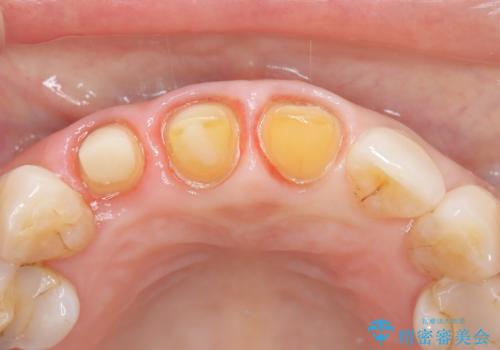

【外傷歯】根管治療から被せ物まで。

- 外傷により他院で治療中に転院を希望され受診されました。

前医では、抜歯も提案をされていましたが適切に治療を行うことで歯を保存することができました。

歯槽骨内水平性歯根破折は、抜歯の適応ではありません。